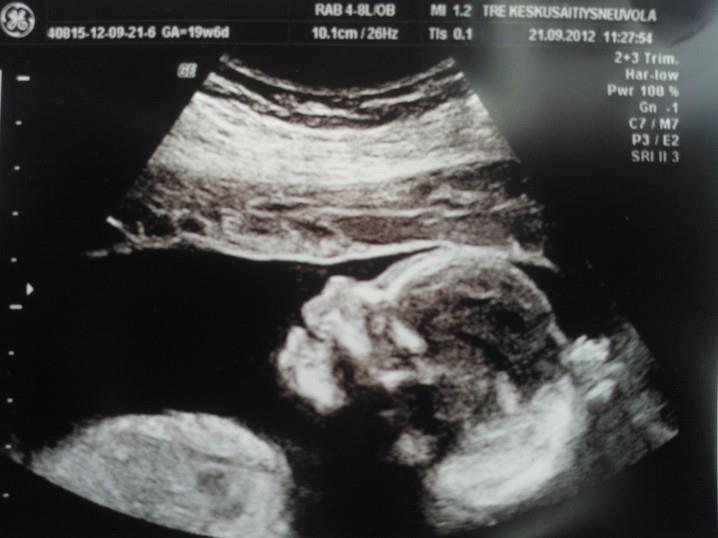

Tänään oli sitten jälleen kerran neuvolakäynti. Painoa taas tullut kilon lisää turvotuksen takia. Verenpaine oli koholla 140/90 ja 133/89, mutta pissa puhdas. Vauvalla kaikki hyvin. Oltiin sunnuntaina eli 27.1 käymässä taysissa, kun oli ollut siitä edeltävänä yönä heikko olo ja päivällä vielä huimas ja näki välillä sellasia "pilkkuja" ilmassa. Sairaalassa mut laitettiin käyrälle 20 minuutiksi. Vauvalla syke hyvä ja vaihteleva niin kun pitääkin olla ja liikkeitäkin oli hyvin tullut. Vauvaa ultrattiin ja sielä oli kaikki kunnossa. Hyvät virtaukset yms.. Syntymäpaino arvioksi saatiin 3,3 kg ja vauvalla on kuulemma urheilijan vartalo :)